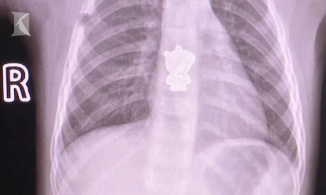

Bé mới 14 ngày tuổi đã có khối u máu trong gan buộc phải cắt bỏ